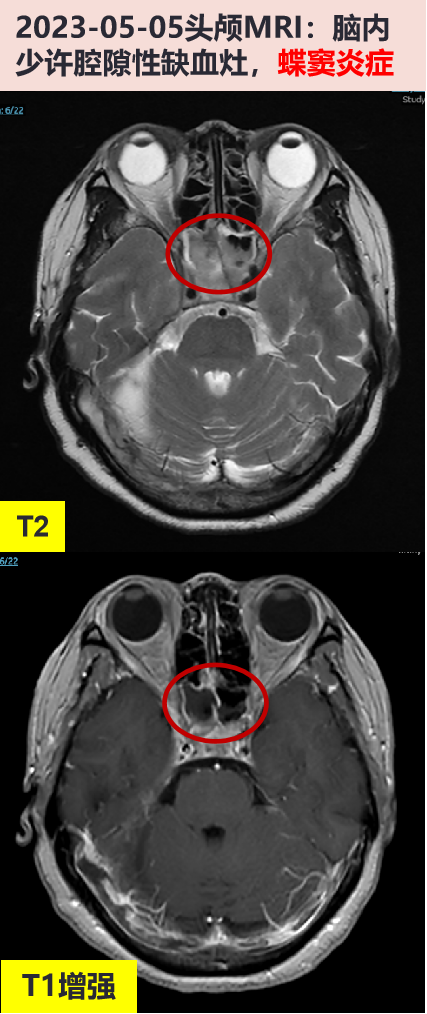

2023-05-05 头颅mri增强:脑内少许腔隙性缺血灶,蝶窦炎症